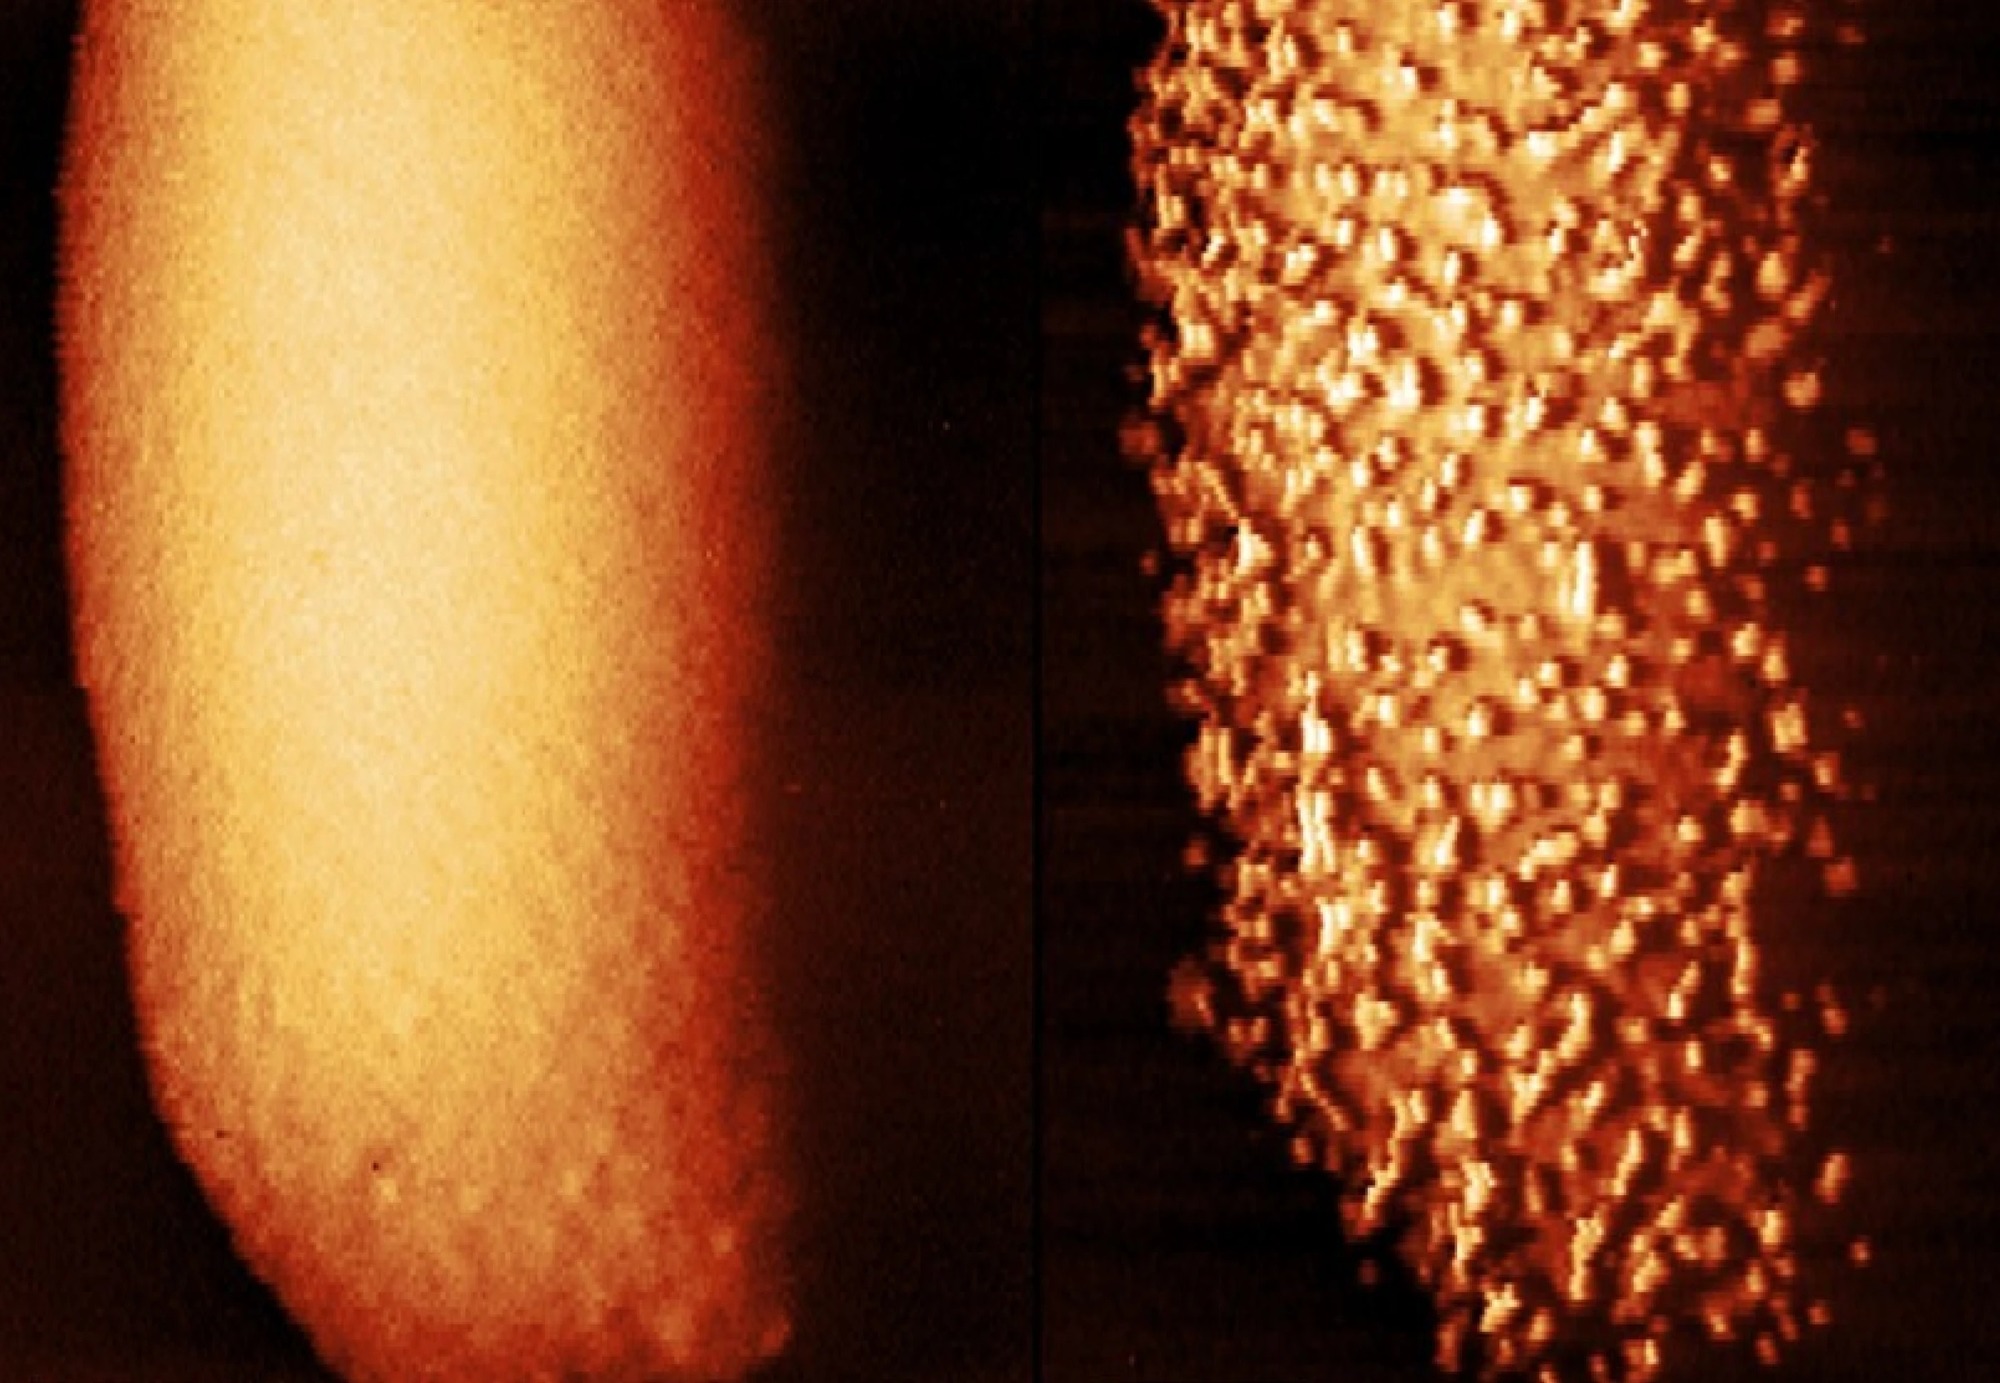

მეცნიერებმა გამოაქვეყნეს სურათები, რომლებშიც დეტალურად ჩანს, როგორ ანადგურებს პოლიმიქსინის ტიპის ანტიბიოტიკები ბაქტერიებს. ეს პრეპარატები დაავადებების გამომწვევი მიკროორგანიზმების მემბრანას აზიანებს და მათ შიგნით აღწევს.

პოლიმიქსინები მკვლევრებმა ნაწლავის ჩხირებზე გამოცადეს. კადრებში ჩანს, როგორ იცვლება მათი უჯრედული სტრუქტურა ანტიბიოტიკის გავლენით, კერძოდ უსწორმასწორობები და ამოზნექილი უბნები შეინიშნება. ამის შემდეგ მიკრობს გარე მემბრანა სცილდება და მედიკამენტს გზა უთავისუფლდება.

ამ ანტიბიოტიკების მოქმედების მექანიზმი გრამუარყოფითი ბაქტერიების ორი მემბრანიდან ყველაზე გარეთას მიზანში ამოღებაა, რადგან იგი ერთგვარი ჯავშნის ფუნქციას ასრულებს. ის, თუ როგორ აღწევს პრეპარატი შიგნით, გაურკვეველი იყო. ახლა მეცნიერებმა აღნიშნული პროცესის ამსახველი სურათები რეალურ დროში გადაიღეს, რისთვისაც ატომური ძალის მიკროსკოპი გამოიყენეს. ეს მეთოდი ბაქტერიის ზემოდან სპეციალური ნემსის მიახლოებასა და დაშორებას გულისხმობს, რათა მათი ფორმა დეტალურად აღიბეჭდოს.

ამან ავტორებს იმის გადაღების საშუალება მისცა, თუ როგორ შეიცვალნენ მიკრობები ანტიბიოტიკის ზემოქმედების შედეგად. კადრებში ჩანს, რომ ნაწლავის ჩხირების მემბრანაზე მალევე გაჩნდა პაწაწინა ამობურცულობები, რომელთა ზრდამაც "ჯავშანი" გაარღვია. დარჩენილ ნაპრალებში ანტიბიოტიკმა შეაღწია და უჯრედები დახოცა.